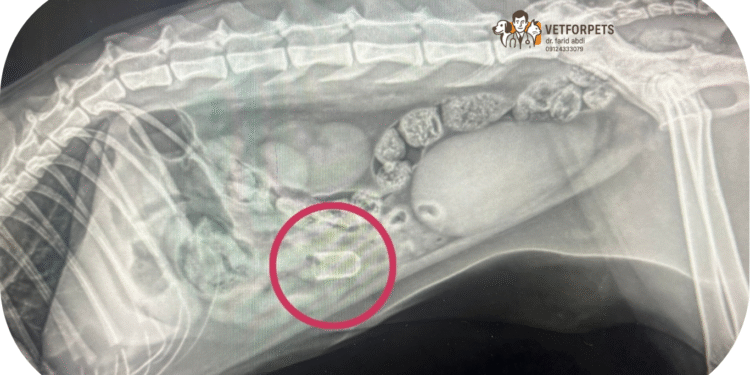

• تصویربرداری: اشعه ایکس یا سونوگرافی محل جسم خارجی را مشخص می‌کند.

•  استفاده از ماده حاجب:  زمانی که جسم خارجی از نوع پارچه یا پلاستیک باشد، تشخیص آن کمی دشوار است. زمانی که پت ها این اشیاء را می‌خورد و در عین حال معده اش پر از غذا باشد از ماده ای تحت عنوان ماده حاجب استفاده می‌کنیم که باعث مشخص کردن جسم خارجی می‌شود.در این روش ماده حاجب را که همان باریوم سولفات است در آب حل می‌کنیم و با توجه به وزن، مقداری از آن را به پت می‌خورانیم سپس بلافاصله از دستگاه گوارش عکس رادیولوژی تهیه می‌کنیم.